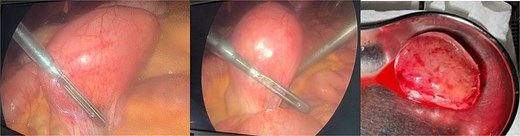

Histopathology examination of our rare case confirmed the diagnosis of acute appendicitis. Gross examination, the mesenteric mass (6 cm) (Fig. 7). Microscopically, it displayed a mixed lymphoplasmacytic infiltration, hyalinized arteries that resembled ‘lollipops,’ and an enlarged lymph node with retrograde follicles. Immunostains revealed polytypic plasma cells, CD20+ B cells, a few CD10+ germinal centers, CD3+/CD5+/CD8+ T cells, a disturbed CD21/CD23 meshwork, and CD31+/CD34+ endothelium. HHV8 stain is negative, and Epstein-Barr virus (EBV) stain showed rare positive cells consistent with past infection (Fig. 8). Serology for HHV8 and HIV is negative.

Microscopically, (a) HE × 100: Lymph node showing regressive lymphoid follicles with small and ‘twining’ germinal centers (GC) (arrow). (b, d) HE × 200: Inter-follicular vascular proliferation. (c) HE × 400: Expanded mantle zone, tend to form concentric rings, ‘onion skin pattern’, blood vessels penetrate the GC, ‘lollipop follicle’.